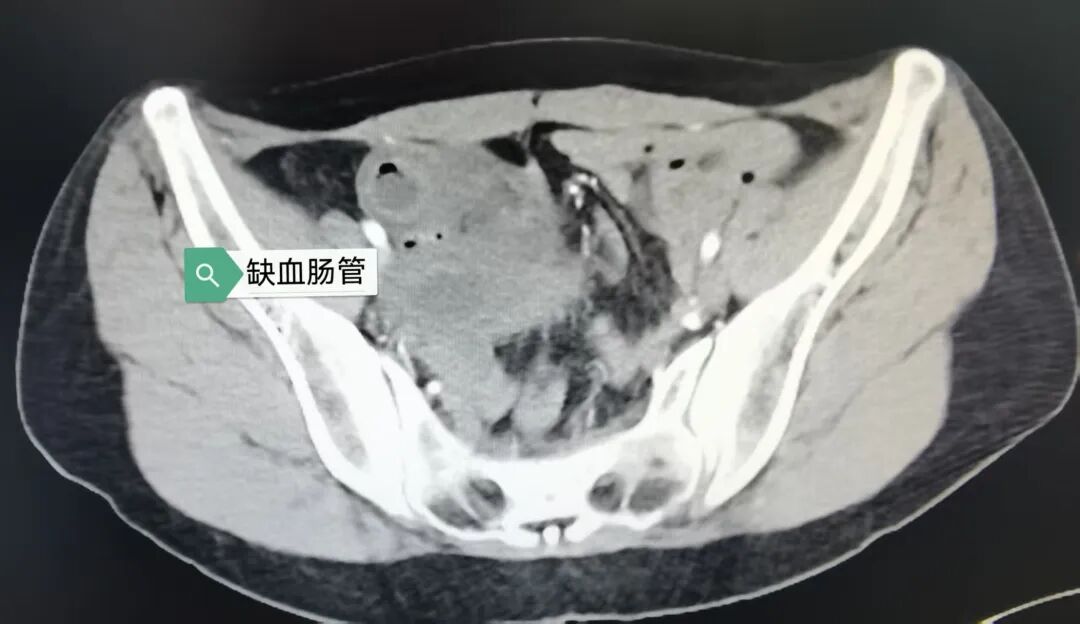

当天下午,被紧急转送至苏州京东方医院急诊科时,小李的脸色已经苍白如纸。急诊科医护人员立即启动绿色通道,腹部增强 CT 检查提示——盆腔右侧急性绞窄性肠梗阻,肠壁已出现缺血改变,盆腔内还有大量渗液。

手术室里,无影灯亮起。当王焕来主任医师团队打开小李的腹腔时,眼前的景象证实了术前的判断:一段约 40 厘米的小肠被粘连的索带卡压,肠壁已经发黑、塌陷,完全失去了生机。

原来,小李此前曾接受过剖腹产手术,术后形成的粘连索带就像一道「隐形枷锁」,缠绕住了她的小肠,导致肠管缺血坏死。这种情况如果延误治疗,可能造成感染性休克、脏器衰竭。